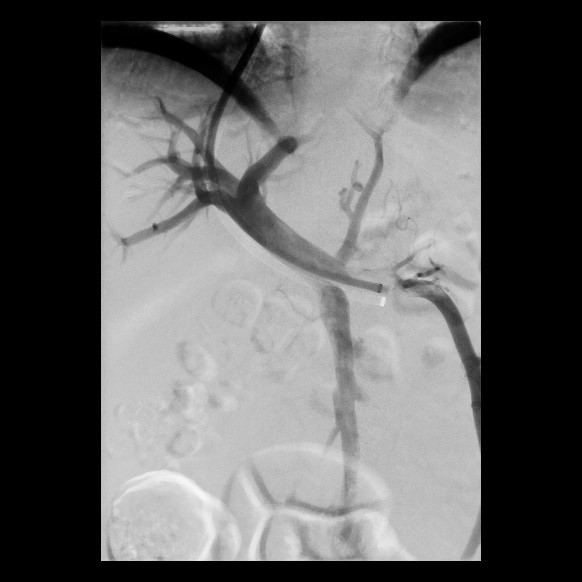

« Zurück Vor perkutaner transluminaler Angioplastie (PTA) der Unterschenkelgefäße (Bild 3 von 4) Vorwärts »

« Zurück Nach perkutaner transluminaler Angioplastie (PTA) der Unterschenkelgefäße (Bild 4 von 4)